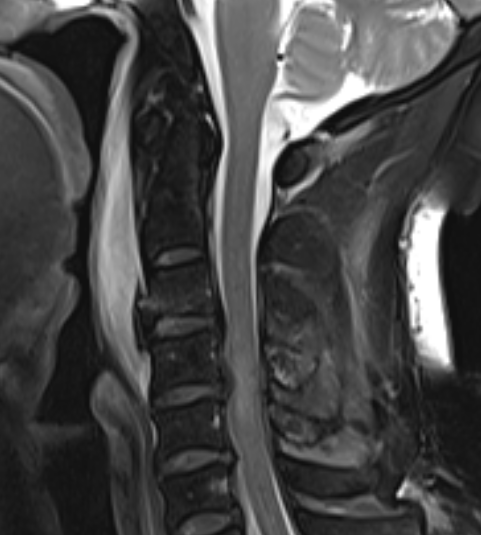

MRI

Teardrop fracture with disruption of ALL with cord contusion and disc prolapse